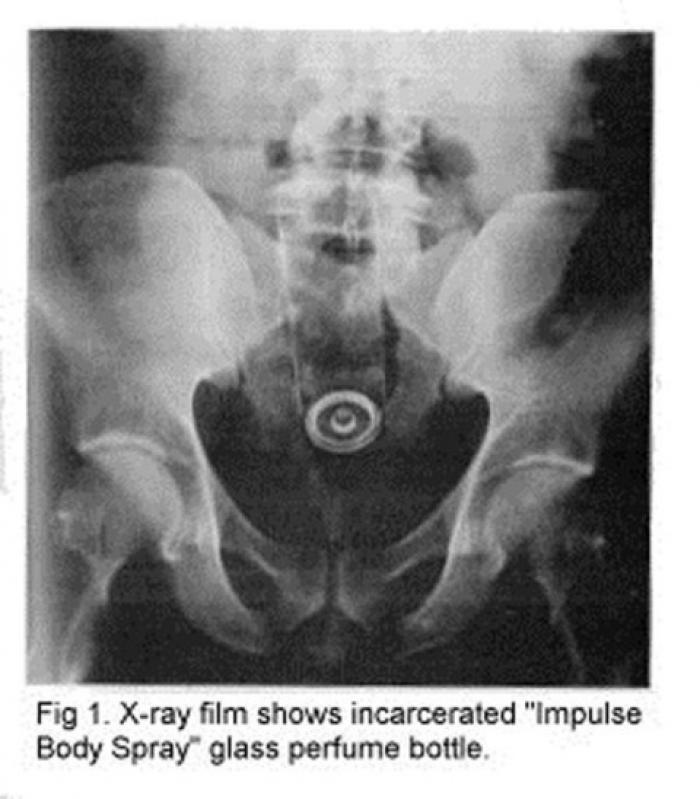

Polițiștii au parte de cele mai amuzante întâmplări, iar infractorii tind să aibă cele mai inventive modalități de a ascunde obiecte, alegând de multe ori posteriorul